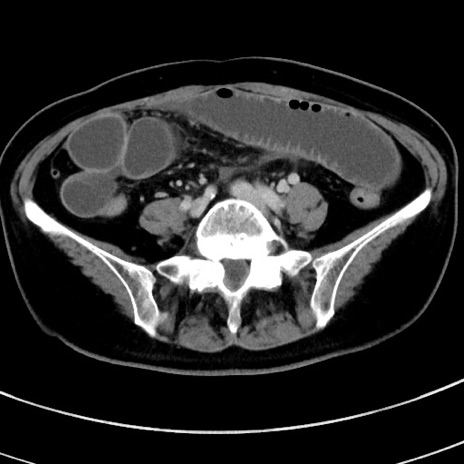

症例9(横断像)

【症例】 60歳代女性

【主訴】むかつき、みぞおちの痛み

【現病歴】3日前よりむかつきがあり、食事がとれない。

【既往歴】糖尿病

【身体所見】発熱なし、心窩部圧痛軽度あるも、腹膜刺激症状なし。

【データ】WBC 7400、CRP 1.92